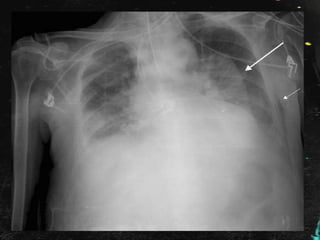

Rx de tórax en planta:

Se comenta el caso al Radiólogo, quien informa

que se trata de una falsa imagen

provocada por pelo largo recogido en moño

o coleta, por lo que es dada de alta con

seguimiento en consulta externa de Medicina

Interna con Rx de Tórax y analíticas; por la

presencia de imagen de vidrio deslustrado en

el TAC poco valorable por la escasa

inspiración de la paciente.

En este caso : Tenía pañuelo que ocultaba el

pelo duro, denso y espeso.

Al realizar la radiografía de tórax:

• Cuello en hiperextensión.

• Densidad del «moño»

Rx de tóraxen planta:

Se comenta elcaso al Radiólogo, quien informa que se trata de una falsa imagen provocada por pelo largo recogido en moño o coleta, por lo que es dada de alta con seguimiento en consulta externa de Medicina Interna con Rx de Tórax y analíticas; por la presencia de imagen de vidrio deslustrado en el TAC poco valorable por la escasa inspiración de la paciente.

Inmigrantes: • Cultura eIdioma. • Hábitos peculiares. • Enfermedades endémicas. En este caso : Tenía pañuelo que ocultaba el pelo duro, denso y espeso. Al realizar la radiografía de tórax: • Cuello en hiperextensión. • Densidad del «moño»